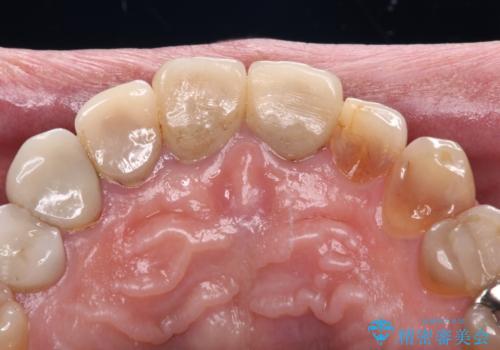

- 前歯のテトラサイクリンによる変色歯と、レジン充填の色の違いを気にして来院された患者様です。

患者様の希望により、前歯6歯をオールセラミッククラウンにて補綴することとしました。